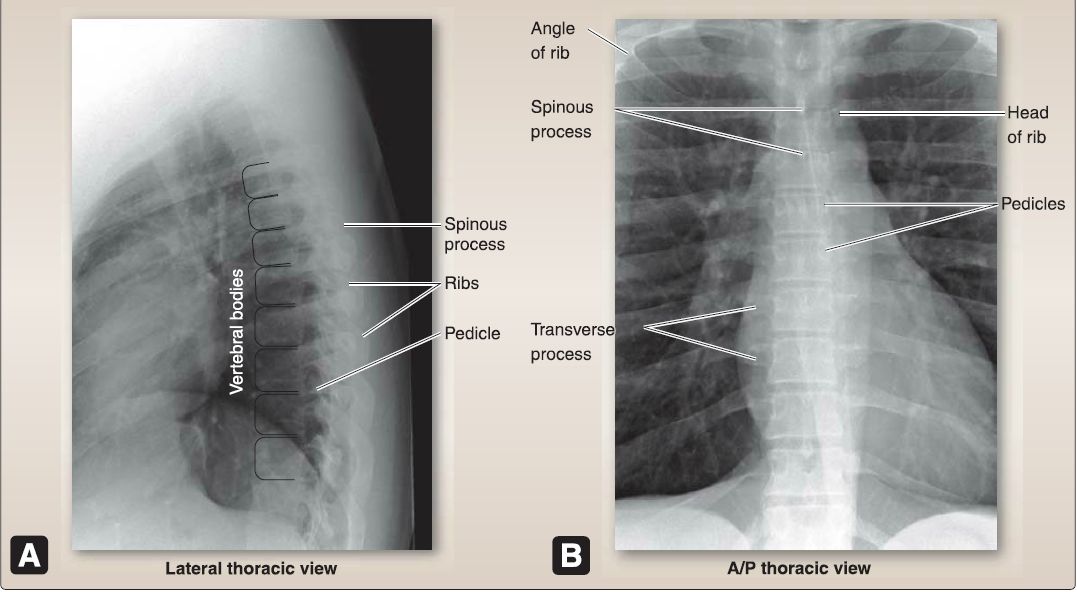

2. Thoracic (T1-T12}: As shown in Figures 5 and 6, thoracic vertebrae feature a heart-shaped body with costal demifacets for articulation with the heads of ribs and a small, circular vertebral foramen. In T1-T10 vertebrae, transverse processes have costal facets for articulation with rib tubercles, articular processes oriented in the frontal (coronal) plane, and long posteroinferiorly sloping, overlapping spinous process.

Figure 5 :Thoracic regional features.

Figure 6: Thoracic plain film views (A and B).